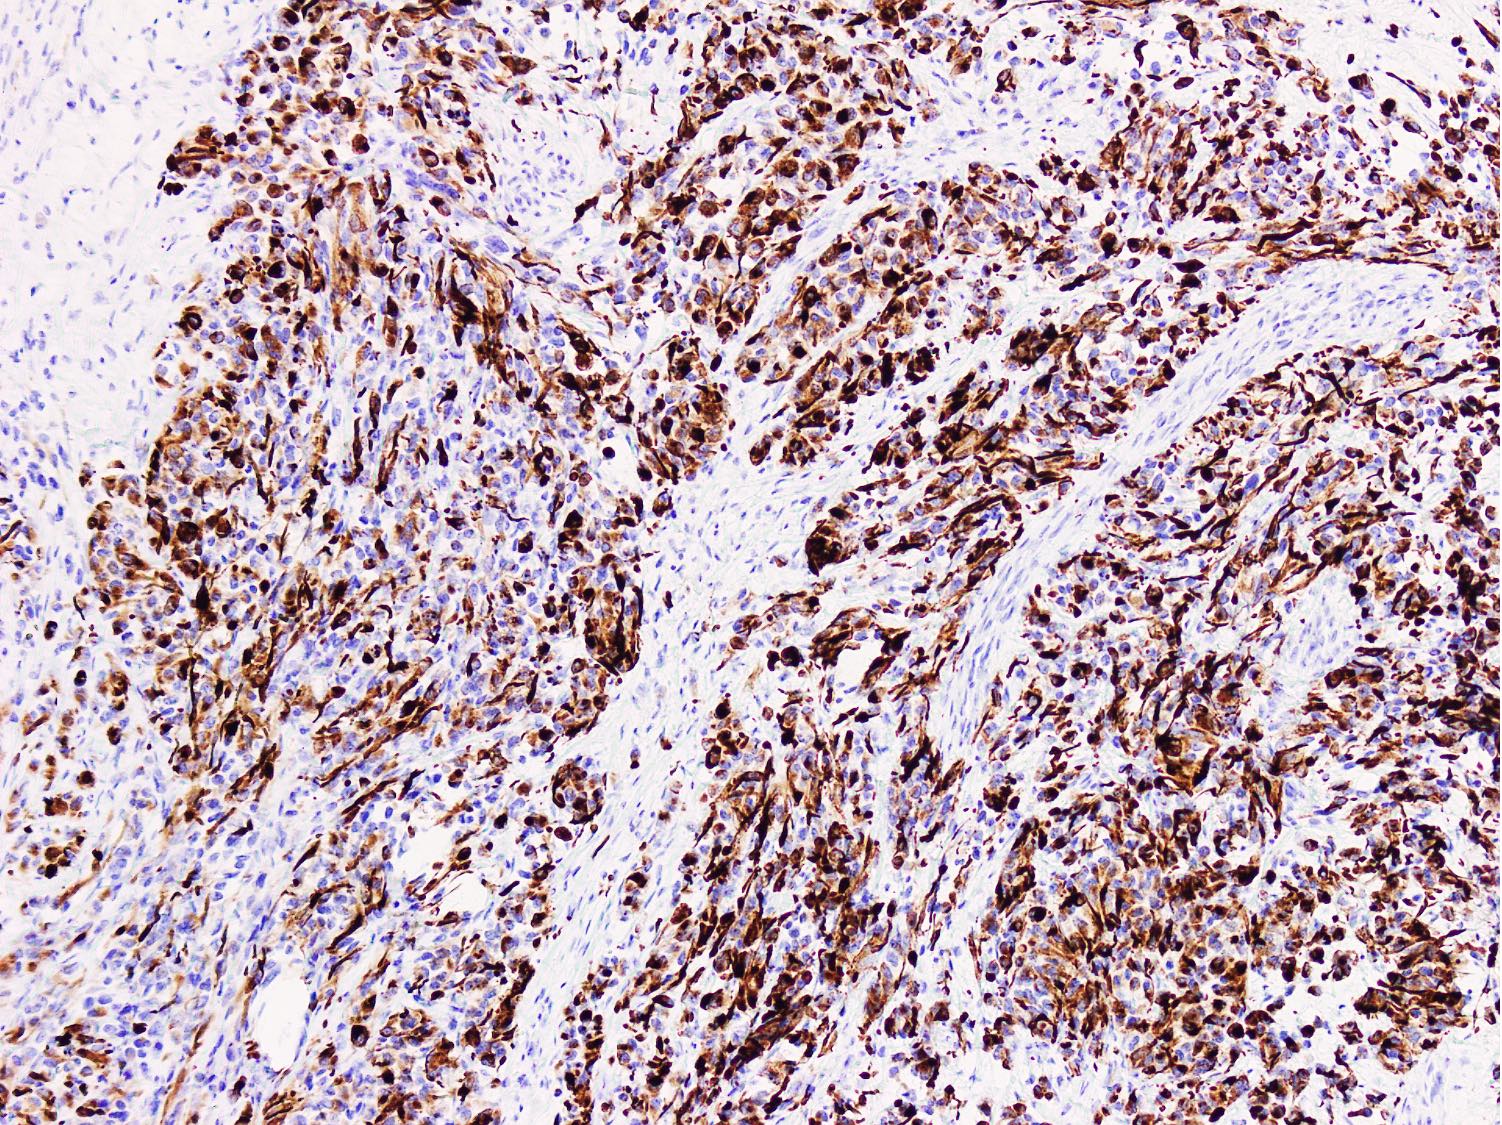

- Diffuse strong myogenin expression

- Small, round, blue cell tumor with diffuse positivity for desmin and myogenin

- Uniform round cells with or without alveolar growth pattern, diffuse homogenous expression of myogenin; heterogeneous expression for desmin or MyoD1; detection of PAX3::FOXO1 / PAX7::FOXO1 fusion by molecular analysis

- Diffuse myogenin expression is an unfavorable prognostic factor (Am J Surg Pathol 2008;32:1513)

Microscopic (histologic) images

Contributed by Nasir Ud Din, M.B.B.S.

Positive stains

- Stains for myogenic differentiation:

- Desmin

- Myogenin (strong and diffuse) (Ann Diagn Pathol 2018;36:50)

- MyoD1 (variable)

- Muscle specific actin (variable)

- PAX3::FOXO1 / PAX7::FOXO1 fusion specific antibodies (Mod Pathol 2021;34:748, Histopathology 2023 Mar 1 [Epub ahead of print])